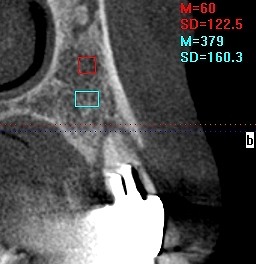

問題の5番になります

動脈も低い位置にありますし、傾斜埋入としました